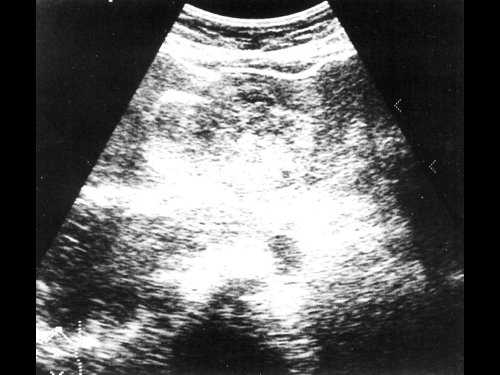

Женщина 50 лет, госпитализирована с болями в верхнем правом квадранте живота. Ультразвуковое исследование органов брюшной полости было проведено в день поступления (рис. 1а, б).

Рис. 1. УЗИ печени.

a) На эхограмме в правой доле печени видны два гиперэхогенных образования с четкими контурами (3,0x1,5 см, 2,5x1,5 см).

б) На эхограмме в левой доле печени видно большое гетерогенное образование (5.0x4.0 см), имеющее дольчатое строение.

Диагноз - множественная гемангиома печени